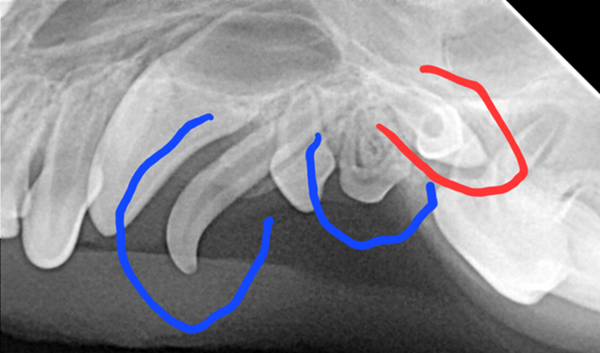

Im Zahnröntgen zeigte sich leider, dass obwohl nur die Spitze des Zahns abgebrochen war (roter Feil), das Lebendige des Zahns (die Pulpa) betroffen war und der Zahn längst abgestorben war. Dies zeigt sich im Seitenvergleich durch eine erweiterte Pulpenkammer (blaue Markierung).

Wir entschieden uns also zu einer Zahnbehandlung in Vollnarkose. Dabei wurden die verbliebenen Milchzähne (blau markiert) gezogen. Auf den Dentalröntgenbildern fiel auf, dass ein bleibender Zahn im Kiefer feststeckte (rot markiert). Dieser würde nach einigen Jahren zur Entstehung einer Knochenzyste beitragen, welche wiederum zu Kieferbrüchen und auch Krebs führen kann. Den verbliebenen Zahn zu ziehen wäre aber sehr herausfordernd gewesen, da er sich auf Höhe eines Kanals im Knochen befand, in dem ein großes Gefäß verläuft und somit ein starkes Blutungsrisiko bestände.

Bei einer Kontrolle nach einigen Monaten stellten wir sehr erfreut fest, dass der Zahn tatsächlich durch den Kiefer in die Mundhöhle durchgebrochen war (rote Markierung).